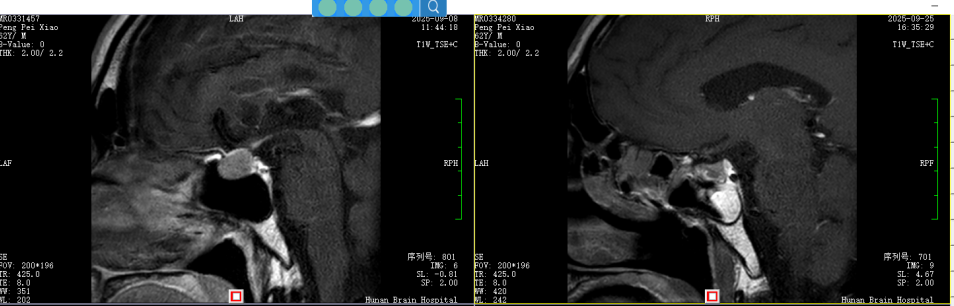

(▲术前术后)

准备充分后,李鑫主任医师、谢志敏主任医师团队为彭先生进行了手术。历时3个小时,团队通过鼻孔这个天然通道,成功切除了鞍区的肿瘤。手术过程顺利,解除了压迫彭先生神经的“元凶”。

半年前,彭先生(化名)开始莫名其妙地头痛,断断续续发作,自己吃了些止痛药也不见好转。最终,他来到湖南省第二人民医院(省脑科医院)神经外科二病区门诊,经过头部核磁共振(MRI)检查,发现他的大脑“鞍区”有一个占位病变,很可能是垂体瘤。